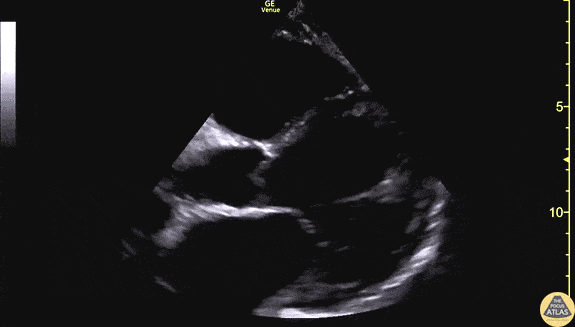

60s M with no known PMH presented to the ED with 3 weeks of progressive dyspnea and bilateral leg edema. POCUS was performed to assess his cardiac function. This clip demonstrates the parasternal long axis and apical 4-chamber views, showing markedly globally reduced LV function, and the endocardium is well seen here. The patient was admitted for further evaluation of his newly diagnosed cardiomyopathy, and formal echocardiography revealed a subtle apical LV thrombus which is not well seen on this POCUS. Dr. Matthew Riscinti Denver Health Medical Center